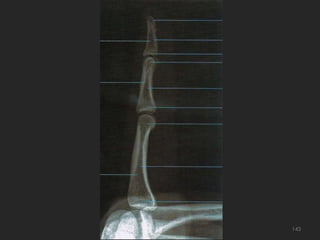

Incidência lateral (lateral-medial ou médio-lateral) dos dedos141

142

143

Incidência oblíqua PA dos dedos – rotação medial ou lateral144